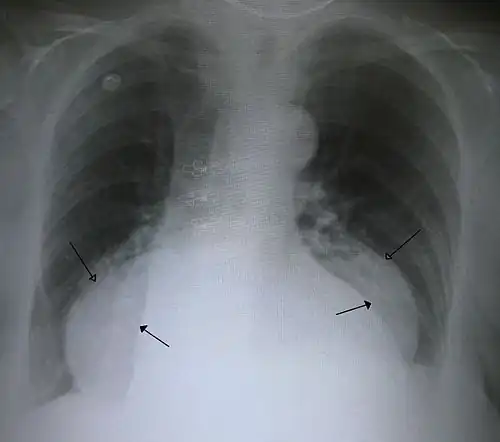

-

A large hiatal hernia on chest X-ray marked by open arrows in contrast to the heart borders marked by closed arrows

This hiatal hernia is mainly identified by an air-fluid level (labeled with arrows). -